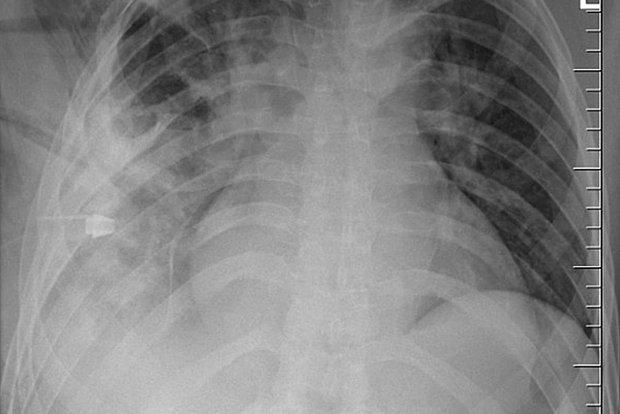

44-летний мужчина обратился в больницу из-за гнойных выделений в районе соска. Врачи удивились, что мужчина не жаловался на боли в груди, проблемы с дыханием и кашель, и сделали ему рентген. Тогда они и обнаружили, что внутри пациента застрял нож. Лезвие вошло рядом с правой лопаткой и не задело ни одного органа, поэтому он спокойно жил с ним.